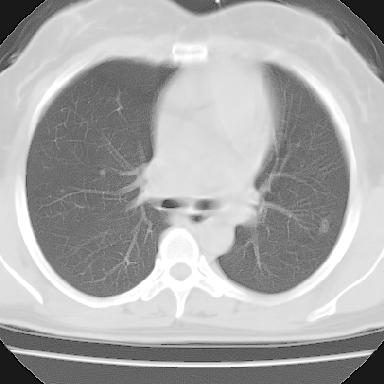

f 37 咳嗽1周,咯血1次,无浓痰,无明显发热

左下肺肿块影,内可以见小泡征,并见厚壁空洞形成,洞内缘凹凸不平,可见壁结节。靠近胸膜侧可见胸膜凹陷征。左侧胸腔内可见少量低密度积液影。右肺可见两处高致密的小结节影。

考虑:左下肺周围型肺癌伴右肺转移

左下肺肿块影,内可以见小泡征,并见厚壁空洞形成,洞内缘凹凸不平,可见壁结节。靠近胸膜侧可见胸膜凹陷征。左侧胸腔内可见少量低密度积液影。双肺可见多发性小结节影。

考虑:左下肺癌性空洞伴两肺转移